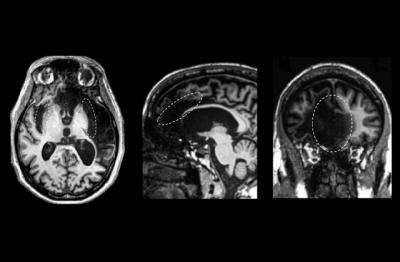

Self-awareness is defined as being aware of oneself, including one's traits, feelings, and behaviors. Neuroscientists have believed that three brain regions are critical for self-awareness: the insular cortex, the anterior cingulate cortex, and the medial prefrontal cortex. However, a research team led by the University of Iowa has challenged this theory by showing that self-awareness is more a product of a diffuse patchwork of pathways in the brain – including other regions – rather than confined to specific areas.

The UI researchers estimate that Patient R has ten percent of tissue remaining in his insula and one percent of tissue remaining in his anterior cingulate cortex. Some had seized upon the presence of tissue to question whether those regions were in fact being used for self-awareness. But neuroimaging results presented in the current study reveal that Patient R's remaining tissue is highly abnormal and largely disconnected from the rest of the brain.